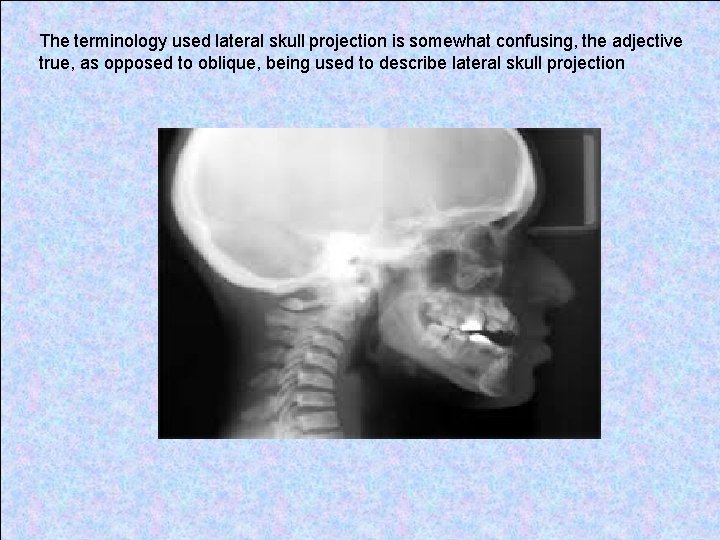

The terminology used lateral skull projection is somewhat confusing, the adjective true, as opposed to oblique, being used to describe lateral skull projection

The film is parallel to the sagittal plane of the patient's head. The X-ray beam is perpendicular to film and sagittal plane.

In addition, the word cephalometric should be include when describing the true lateral skull radiograph taken in the cephalostat. This enables differentiation from the non-standardized true lateral skull projection taken in a skull unit.